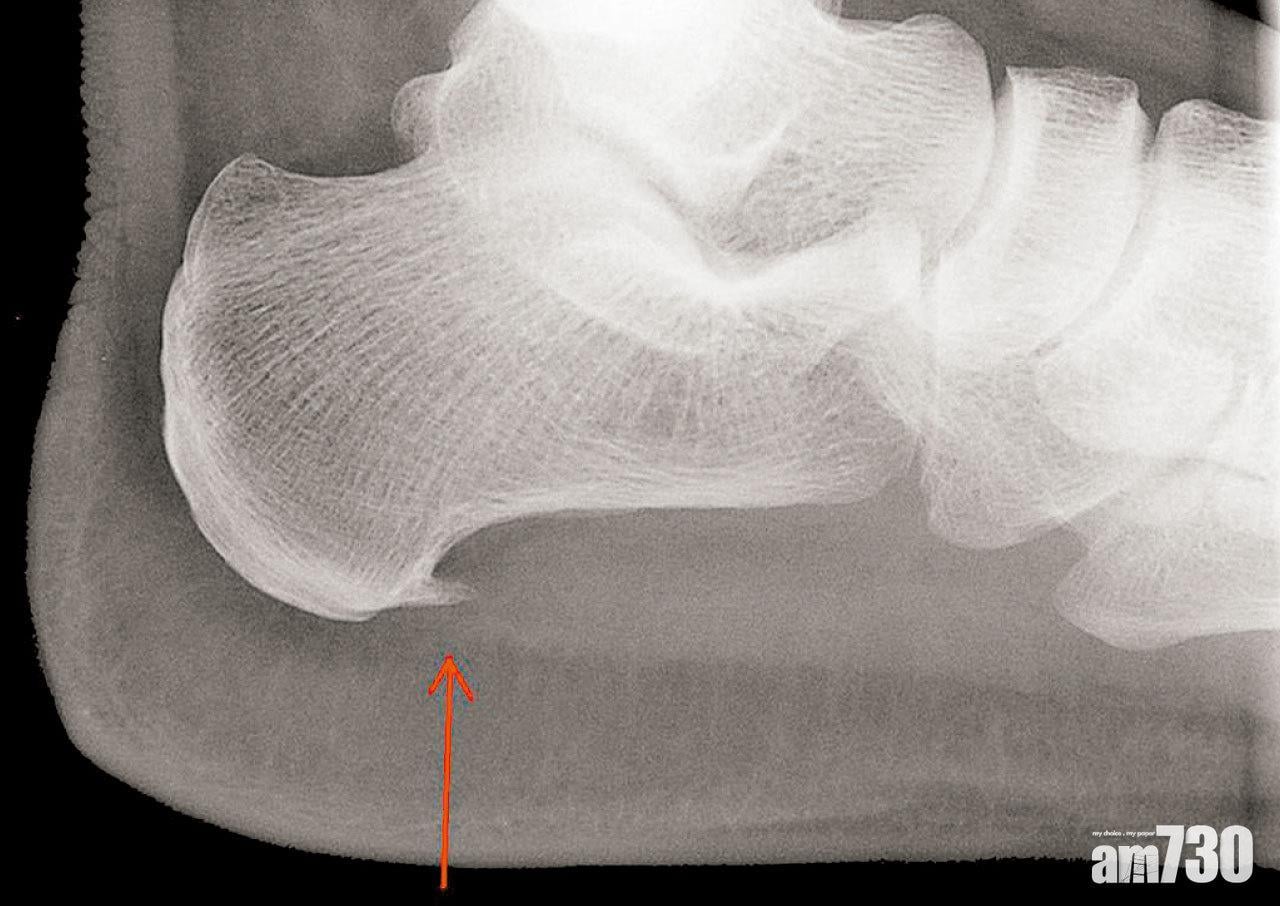

很多人聽到骨刺都毛骨悚然,其實骨刺並不像刺,它是骨頭生上突出的平滑小骨,通常形成在兩塊骨頭中間的關節,而且很多時候都沒有病徵。手指節是較常影響到的地方,患者通常會發現手指關節腫脹,戒指也漸漸戴不下,部分病人更感到痛楚,影響生活。有時,骨刺生長會在膝關節,影響走路,或令患者不能伸直雙腳。至於肩膊的骨刺,會刺激旋轉肌,引致痛楚並減低肩膊活動的幅度。當髖關節受影響時,患者走路會感到痛楚。至於長在脊椎的骨刺,則有可能壓在脊髓或神經線上,導致背部、手和腳麻痹和乏力。

骨刺最常見的成因是骨關節炎,這主要是由於長期勞損和退化導致,因此多影響長者。有時,運動創傷和意外等原因,亦會導致一些較年輕的人患上骨關節炎。其實,關節發炎和受傷,均會導致骨末端的軟骨勞損和退化。當身體嘗試修補受損的軟骨時,會在附近長出骨刺。年紀愈大,長出骨刺的風險愈高。然而,一些結構上的問題,例如脊柱側彎,不良的姿勢和反覆勞損性的動作亦會誘發骨刺形成,當中也有遺傳因素。此外,一些風濕免疫病,例如脊椎關節炎和銀屑病關節炎患者,如沒有得到及時控制也會導致骨刺形成。